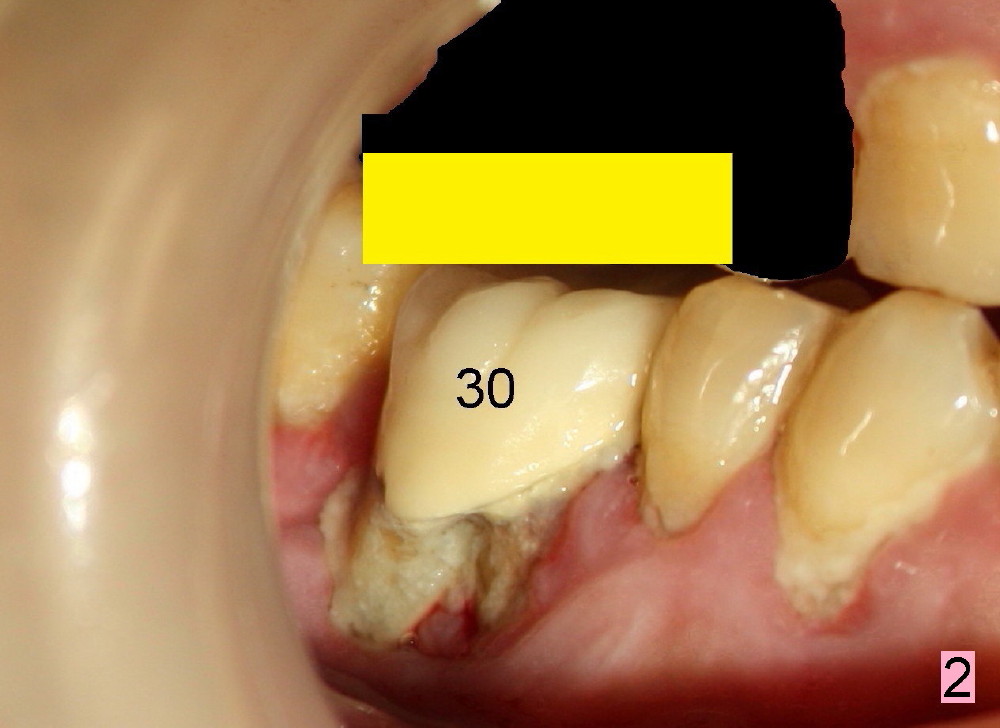

Regular posterior periapical (PA) device has a horizontal bite block (Fig.1: B). The latter rests on the occlusal surface of the posterior teeth to be taken radigraphically (Fig.2 illustration: yellow rectangle). This typical PA image shows the whole teeth including the crowns and the roots, but it does not catch the whole image of the inferior alveolar nerve as related to implant placement (Fig.3 N). The tooth #30 has complex endo-perio disease and is going to be extracted and restored by an implant.